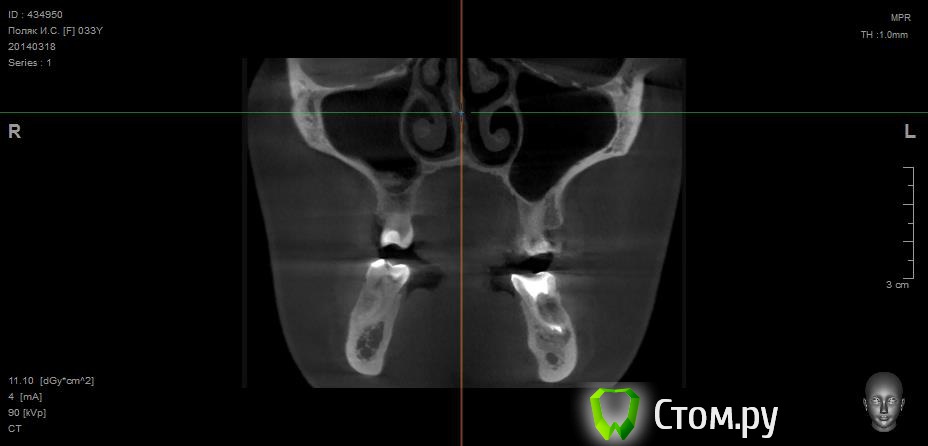

Майло Опубликовано 18 марта, 2014 Автор Поделиться Опубликовано 18 марта, 2014 (изменено) Здравствуйте, наконец сделала кт. Сегодня появилась небольшая боль над правой бровью (после лазера прошла, к вечеру появилась опять). Насморк и заложенность присутствуют. Еще сегодня опять поговорила со своим хирургом имплантологом. По симптомам сказал, что похоже присоединилась какая-то лор болячка и наверное надо сходить к лору. По кт сказал, что все нормально. Немного сужена пазуха справа, но учитывая, что я аллергичная, это нормально. Про капли типа Полидекса, сказал спросить у лора. Завтра я делаю последний лазер, по прежнему промываю нос Отривином Бэби (мне так удобней), пью кларитин, "выбиваю" нос по необходимости, но стараюсь пореже (2-3 раза в день). Еще он отдал кт через 2 недели после имплантации, на всякий случай прикреплю и этот снимок. Самый первый снимок кт был сделан через 2 недели после имплантации. Второй и третий сегодня. Подскажите, я так понимаю данное кт не показывает есть ли у меня гайморит? (к лору смогла записаться аж на 26-е) И все равно хотелось бы узнать ваше мнение по поводу состояния имплантов, есть ли там воспаление или "нагноение"? Изменено 18 марта, 2014 пользователем Майло Ссылка на комментарий

Майло Опубликовано 18 марта, 2014 Автор Поделиться Опубликовано 18 марта, 2014 (изменено) Решила еще добавить пару кадров своих пазух, вначале показалось что справа что-то есть (рис1), потом поняла это костный материал и импланты (рис2). Надеюсь так должно быть. И еще вопрос, может и "тупой", такое яркое свечение имплантов, особенно заметно на фото в профиль, это нормально? Изменено 18 марта, 2014 пользователем Майло Ссылка на комментарий

Bier Опубликовано 18 марта, 2014 Поделиться Опубликовано 18 марта, 2014 выглядит все неплохо, и пазуха чистая. Гайморита у вас нет. Сходите к ЛОРУ 2 Ссылка на комментарий

Майло Опубликовано 19 марта, 2014 Автор Поделиться Опубликовано 19 марта, 2014 (изменено) выглядит все неплохо, и пазуха чистая. Гайморита у вас нет. Сходите к ЛОРУСпасибо. А такие затемнения вокруг имплатов, это нормально? Изменено 19 марта, 2014 пользователем Майло Ссылка на комментарий

red_butler Опубликовано 19 марта, 2014 Поделиться Опубликовано 19 марта, 2014 Да, это артефакты вызванные металлом Ссылка на комментарий